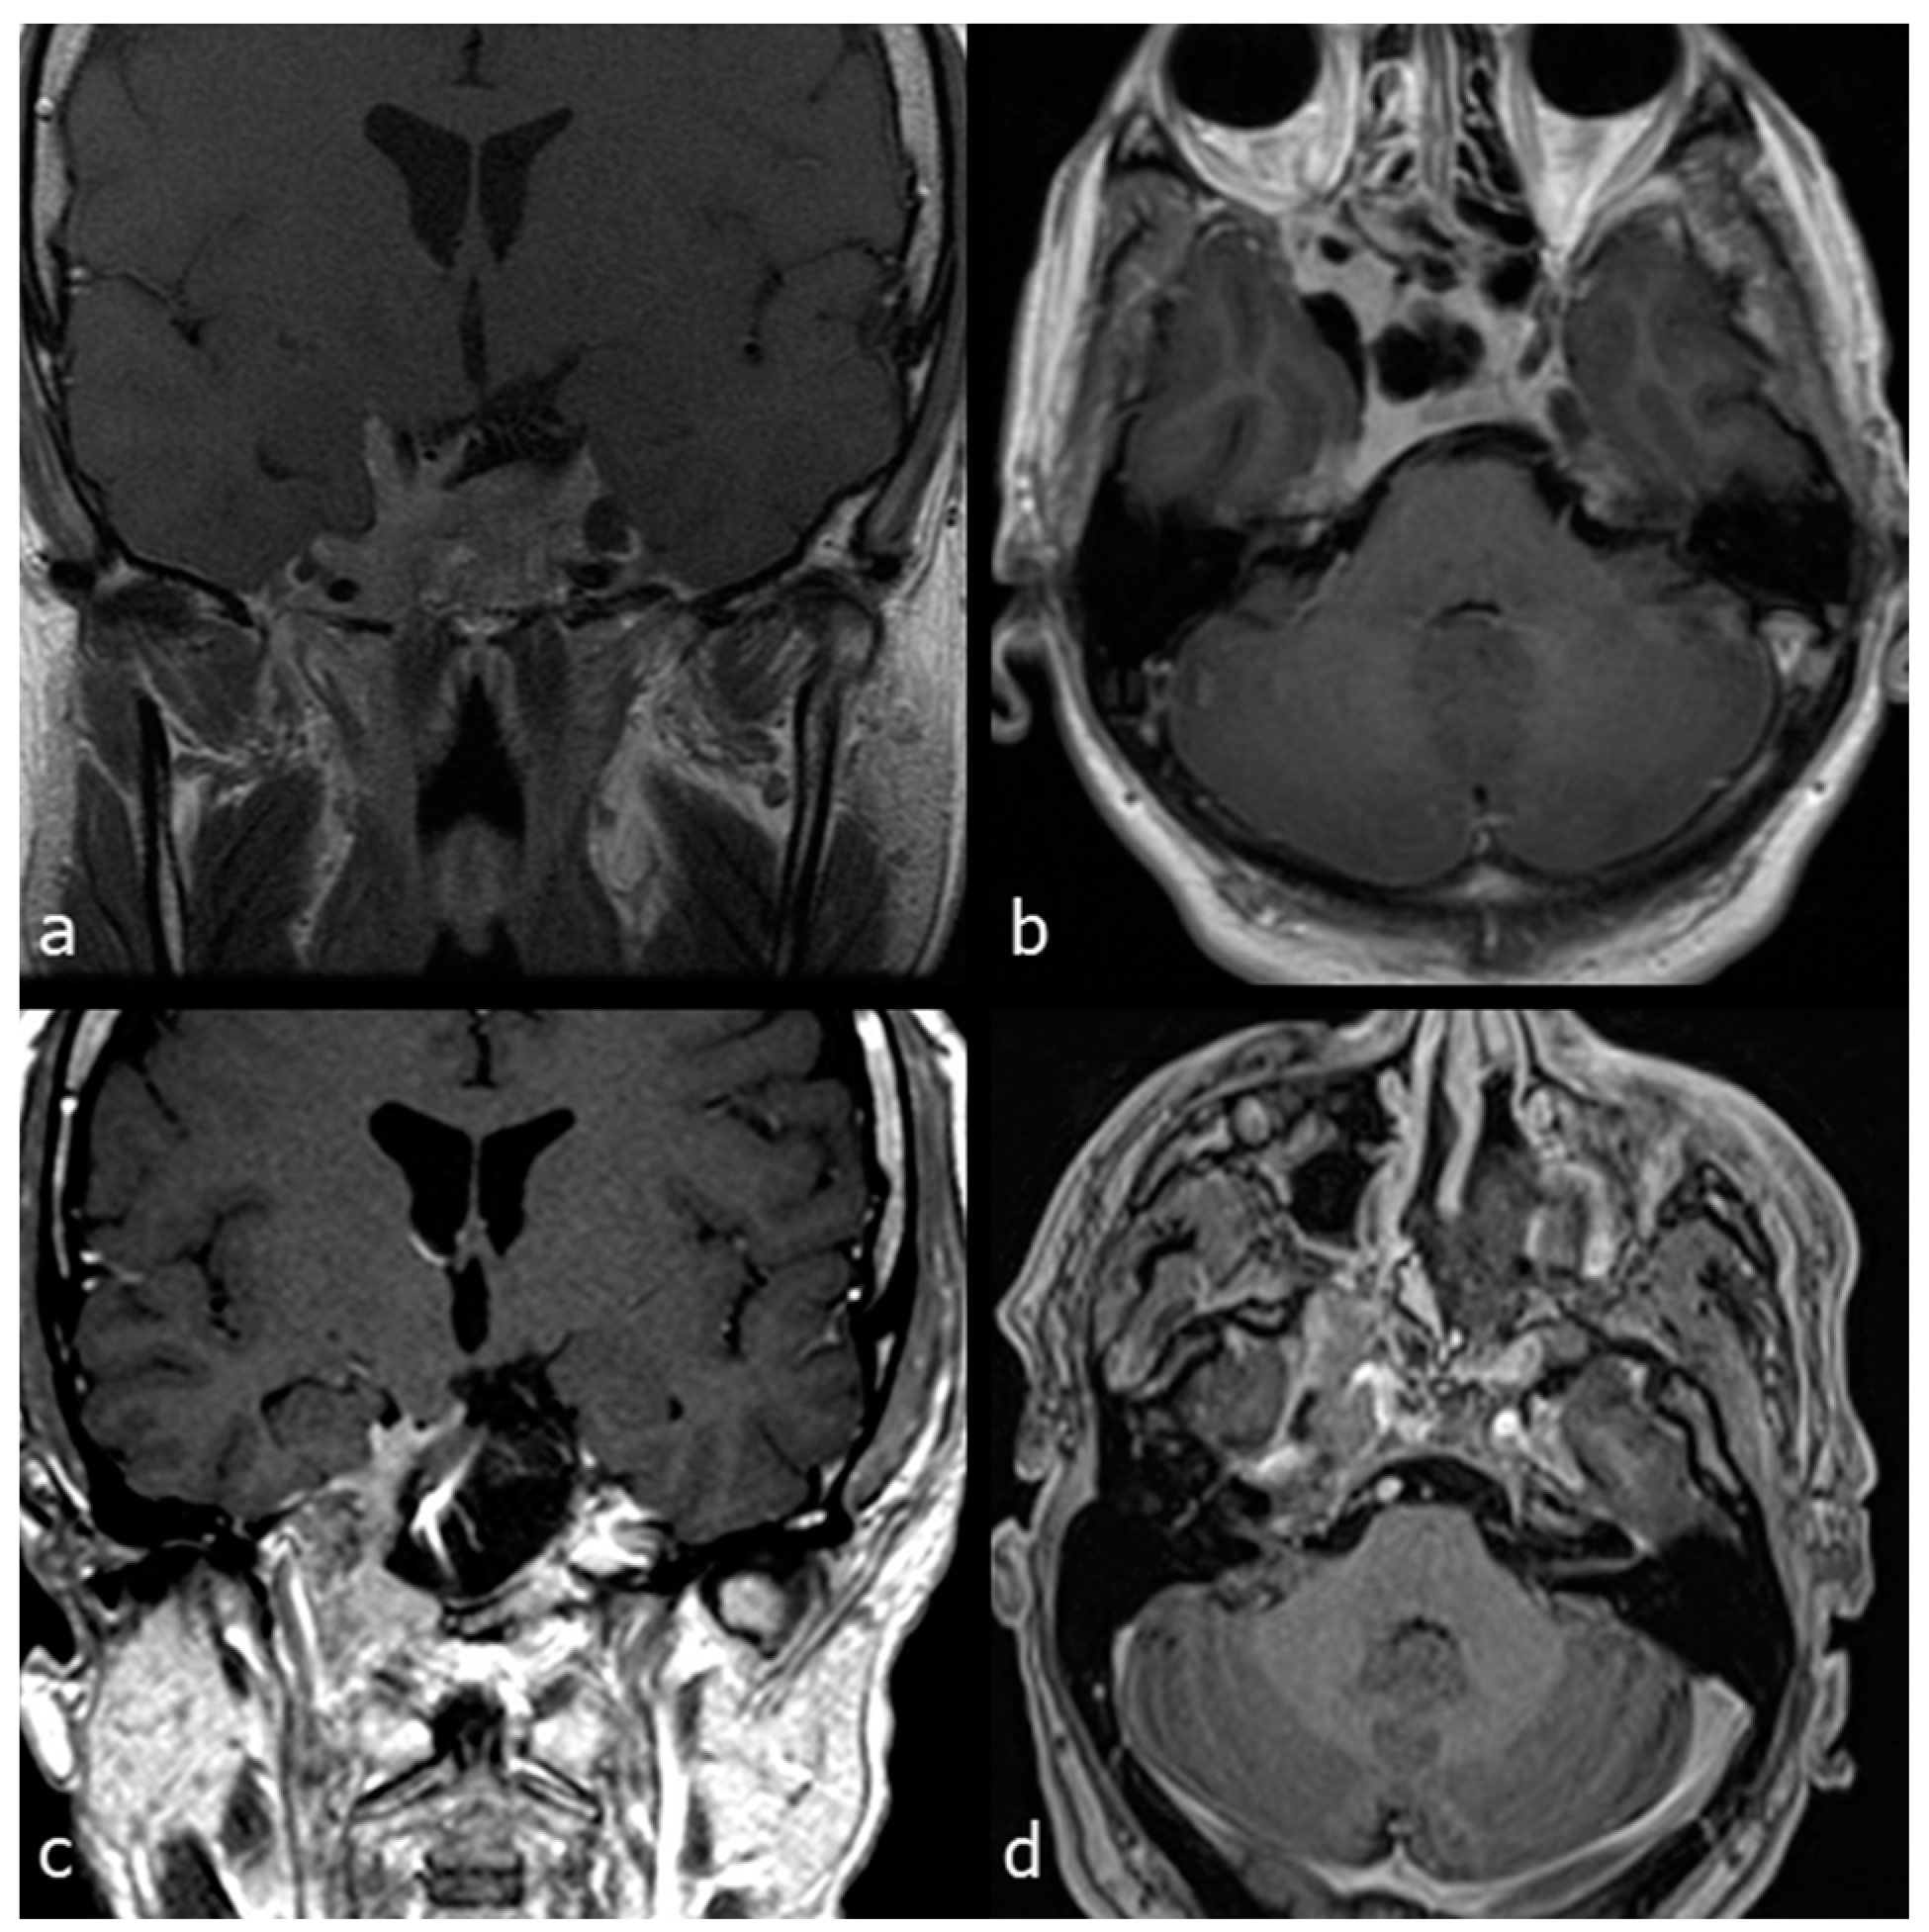

- Case 1

- Case 2

- Case 3